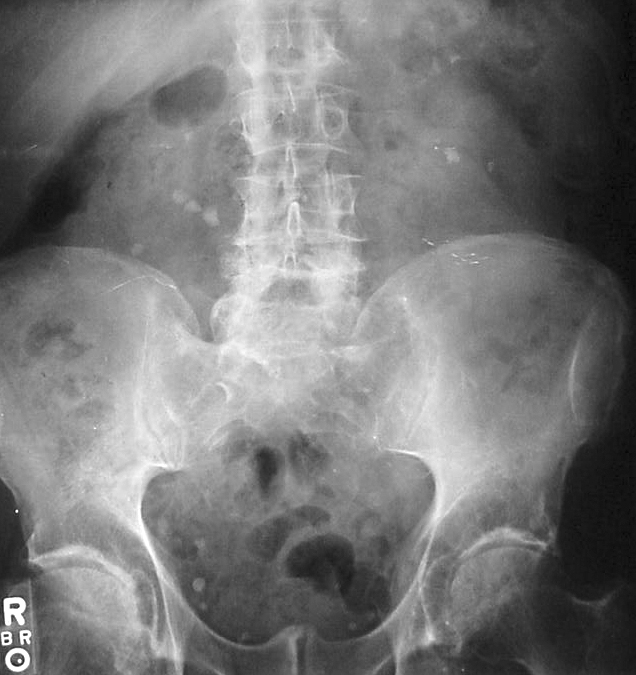

Example 4

Diagnosis

Ankylosing Spondylitis (bamboo spine)